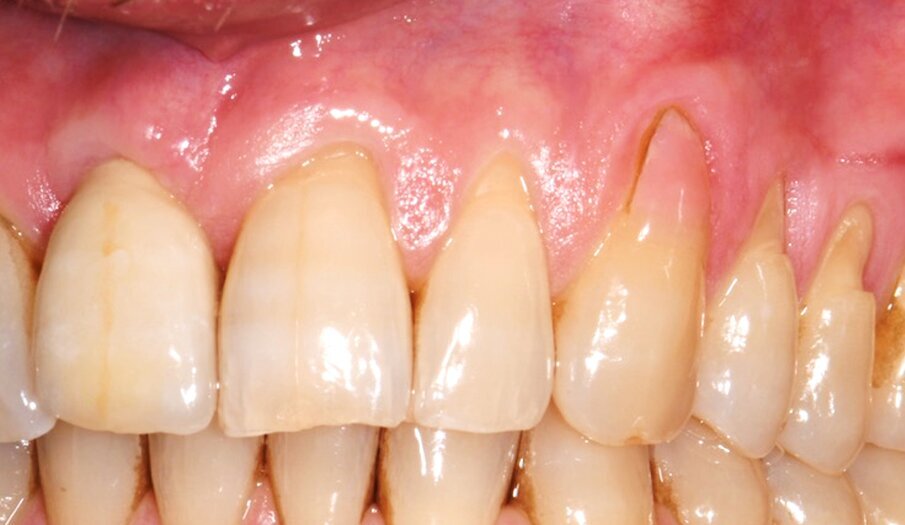

Il caso riguardava un paziente maschio di 38 anni, non fumatore, non affetto da parodontite, che si presentava nello studio per la risoluzione di una recessione gengivale a carico dell’elemento 23, trattato precedentemente con materiale composito (Fig. 1). L’esame clinico evidenziava recessioni multiple nei 4 quadranti associate a lesioni cervicali non cariose (NCCLs). In particolare, erano presenti recessioni gengivali di tipo I a carico degli elementi 21-25 (Fig. 2). Le gengive erano caratterizzate da un fenotipo sottile. Previo trattamento conservativo delle NCCLs eseguito nella settimana precedente a quella dell’intervento, veniva ripristinata la sede della giunzione smalto-cemento in sede 21-25. In accordo con il paziente si conveniva di trattare le recessioni gengivali di tipo I degli elementi 23-25 con una procedura di chirurgia mucogengivale che combinava la tecnica del lembo a posizionamento coronale MCAF e l’innesto di una matrice collagenica tridimensionale di origine equina (XC COLLAGEN Xenomatrix, Bioteck Spa). La sede delle recessioni presentava una sufficiente banda di gengiva aderente (2 mm) che consentiva l’impiego della matrice collagenica. L’area di intervento veniva anestetizzata utilizzando articaina cloridrato 40 mg + 10 µg/ml di adrenalina (Citocartin, Molteni Dental s.r.l). L’intervento per la copertura radicolare veniva eseguito con tecnica MCAF individuando il canino come centro di rotazione del lembo (Fig. 3).

Fig. 2 - Sede delle recessioni da sottoporre a chirurgia MCAF: elementi 21-25 con presenza di NCCLs.